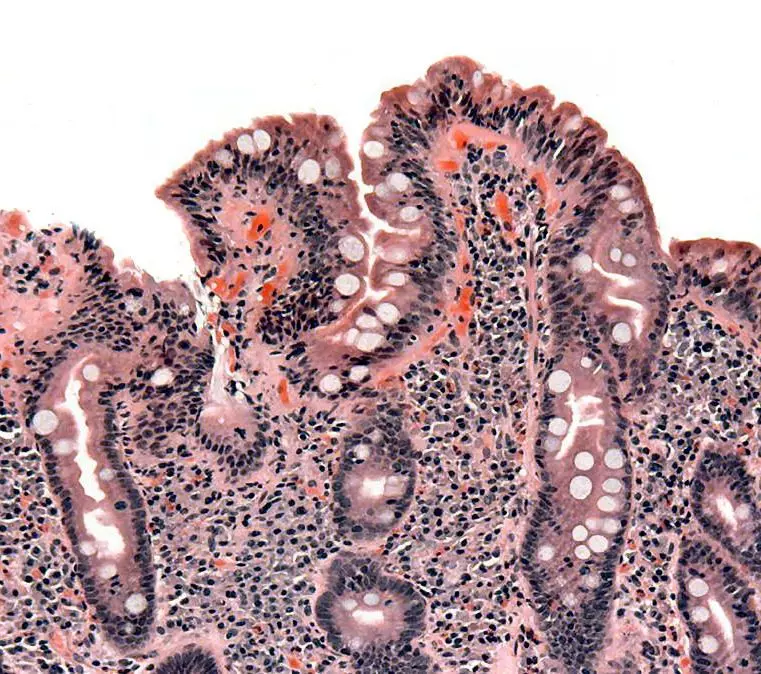

Image - Atrophic villi of Coeliac disease, note the blunted ends of the villi

Coeliac disease is an autoimmune inflammatory condition of the bowel that arises from an immunological response to the gliadin fragment of gluten. This reaction to gluten causes the small bowel to be chronically inflamed, resulting in atrophy of the villi within the intestine and therefore reduced absorption of other nutrients. There is often a genetic link, so a thorough family history is important when diagnosing coeliac disease.